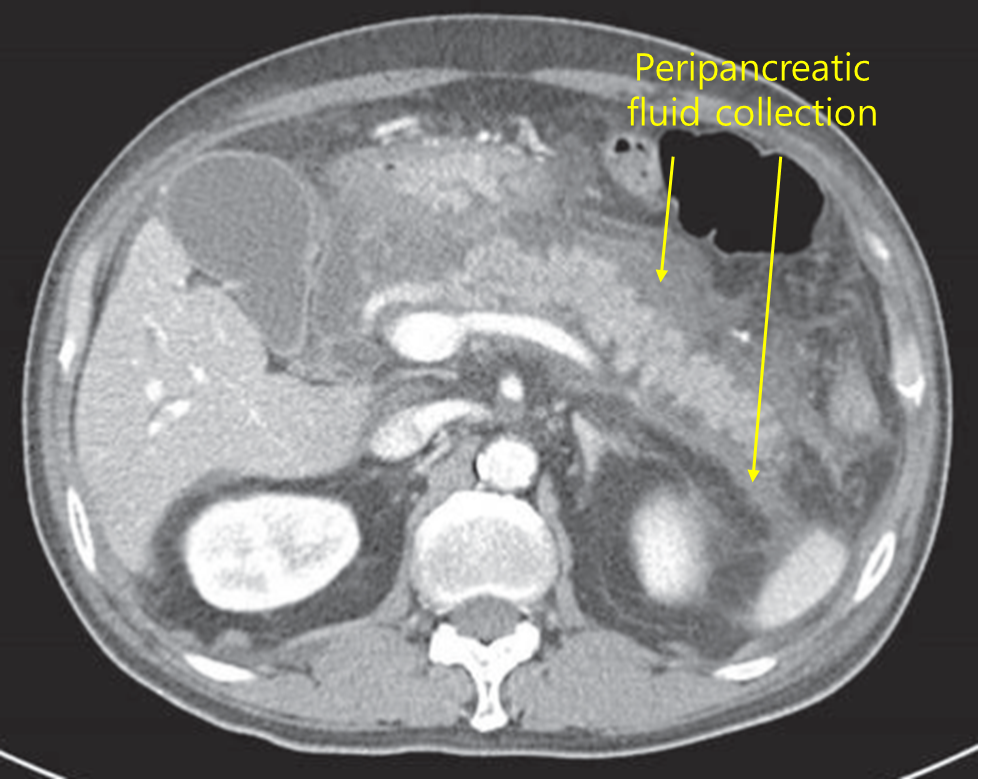

50세 남자가 하루 전부터 명치가 심하게 아프다며 병원에 왔다. 혈압 130/85 mmHg, 맥박 105회/분, 호흡 20회/분, 체온 37.8℃이다. 배 청진에서 장음이 감소되어 있고 배 전체에 압통이 있으나 반동압통은 없다. 혈액검사 결과는 다음과 같다. 복부 컴퓨터단층촬영 사진이다. 치료는?

백혈구 18,000/mm3, 혈색소 13.7 g/dL, 혈소판 165,000/mm3, 총빌리루빈 1.5 mg/dL, 알칼리인산분해효소 195 U/L, 아스파르테이트아미노전달효소 90 U/L, 알라닌아미노전달효소 44 U/L, 아밀라아제 2,880 U/L, 리파아제 3,700 U/L

Img | CT: 췌장 주위 fluid collection |

• 급성 복통을 호소하는 환자로, 혈액검사 상 amylase와 lipase의 상승, CT 상 췌장 주위 fluid collection 소견으로부터 급성 췌장염을 진단할 수 있다. 급성 췌장염의 치료는 대증치료로 금식, 진통제, 수액 공급이 주된 치료이며 보기 중에서 금식을 선택할 수 있다.

진단 | • US: 담석, 담관확장 확인 • CT: 췌장 실질의 edema, 췌장 근처 조직의 inflammation |